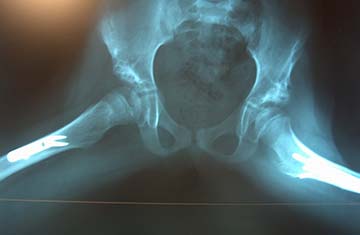

Ιδιαίτερη προσοχή χρειάζεται στην εκτίμηση αμφοτερόπλευρου εξαρθρήματος του ισχίου, όπου δεν υπάρχει εμφανής ανισοσκελία αλλά αξιολογείται η αμφοτερόπλευρη εικόνα περιορισμού της απαγωγής των ισχίων.

Όταν το παιδί αρχίζει να βαδίζει, σε ετερόπλευρο εξάρθρημα του ισχίου υπάρχει εμφανής ανισοσκελία και χωλότητα κατά την βάδιση από την ανεπάρκεια του μέσου γλουτιαίου (Tredelembourg), ενώ σε αμφοτερόπλευρο εξάρθρημα τα ευρήματα είναι λιγότερο εμφανή, με εικόνα νήσσειας βάδισης και αυξημένης λόρδωσης της ΟΜΣΣ. Εμφανίζεται καθυστέρηση στην χρονική έναρξη της αυτόνομης βάδισης.

ΚΛΙΝΙΚΑ ΕΥΡΗΜΑΤΑ

• Περιορισμός απαγωγής ισχίων

• Θετικό σημείο Ortolani – Barlow

• Φαινομενική βράχυνση του άκρου

• Ασυμμετρία στην γλουτιαία πτυχή – βαθιά δερματική πτυχή στην εξαρθρωμένη μηροβουβωνική πτυχή.

• Χωλότητα, με βάδισμα «σαν πάπια» σε αμφοτερόπλευρο εξάρθρημα

• Καθυστέρηση βάδισης

• Φαινομενική βράχυνση

• Θετικό σημείο Tredelembourg